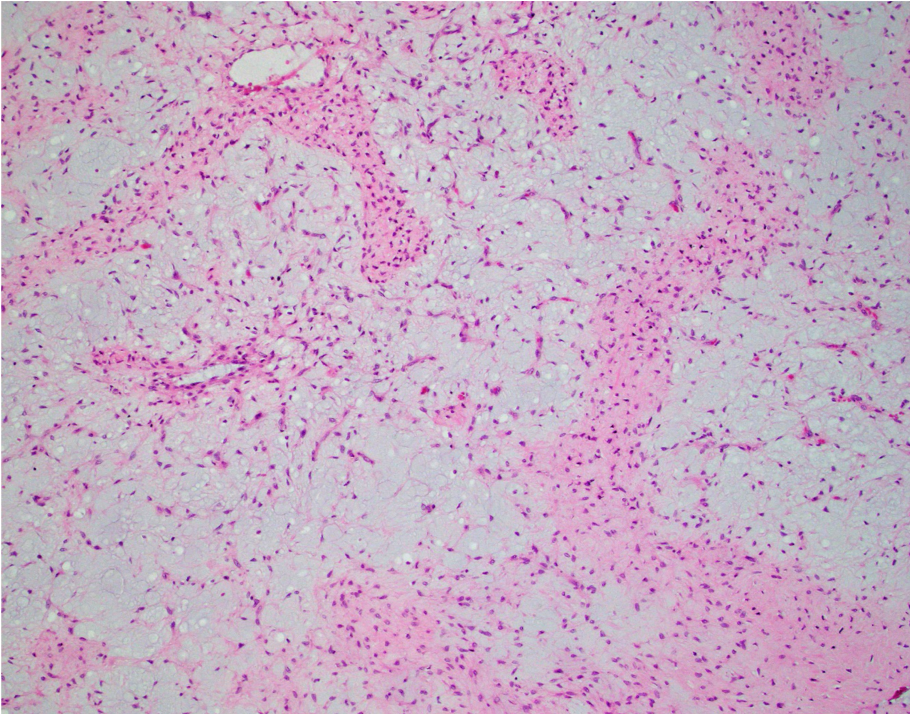

Answer: B.) Chondromyxoid fibroma

Chondromyxoid fibroma (CMF) is a benign neoplasm sharply demarcated from the surrounding bone exhibiting a zonal/lobular architecture. The peripheries of the lobule are more hypercellular and exhibit stellate and spindle-shaped cells and occasional osteoclast-like giant cells. The centers of the lobule are more hypocellular and myxoid with embedded bland stellate and spindle-shaped cells. While the centers of the lobule resemble hyaline cartilage, true hyaline cartilage is rare in CMF.